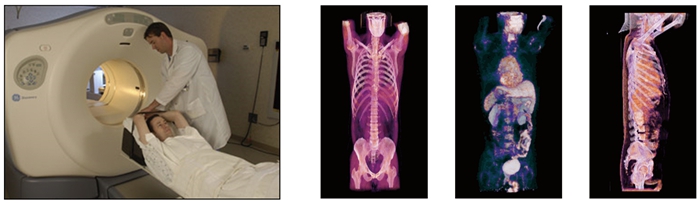

自1895年伦琴发现Ⅹ射线以后,核成像成为认识物体内部结构的主要技术手段。核成像技术能够完整的显示岀人或动物体内细胞或分子水平的生理和病理过程,实现了真正意义上的“功能”成像,为研究重大疾病成因、疾病的早期预防及早期治疗提供了帮助,正电子发射断层扫描仪(PET)、单光子发射断层扫描仪( SPECT)是核成像硏究和应用中最具代表的设备。

人体PET/CT成像

动物PET/CT成像